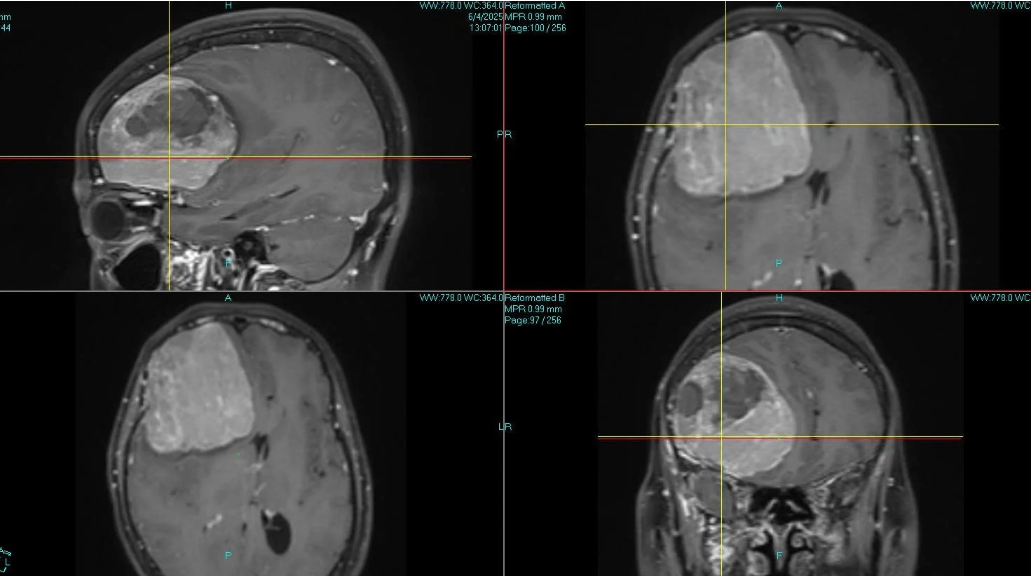

Trước khi nhập viện, các triệu chứng đau đầu, buồn nôn tăng lên nhanh chóng, đến sáng hôm sau bệnh nhân đã lơ mơ, không còn tỉnh táo. Ngay khi nhập viện, các bác sĩ tiến hành chụp cắt lớp vi tính sọ não và phát hiện người bệnh có khối u não kích thước lớn thùy trán phải đang chảy máu.

Hình ảnh khối u não kích thước lớn chảy máu vùng trán phải của bệnh nhân L. Ảnh BVCC